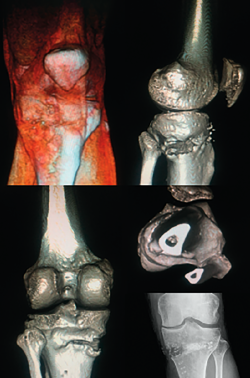

Other tests that contribute to the diagnosis are stress valgus radiographs (local anesthesia infiltration is advised in order not to underestimate the test), magnetic resonance imaging (MRI) and arthroscopic exploration (Figure 1).

Figure 1. Arthroscopic view through the anterolateral port of a positive drive-through sign with abnormal aperture of the internal compartment secondary to insufficiency of the medial collateral ligament. Right knee.